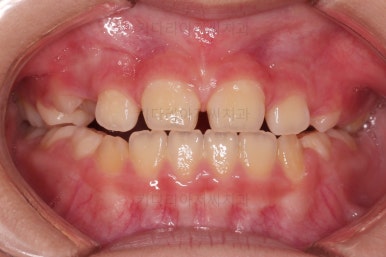

초진 시 입안의 모습입니다.

아래쪽 치열이 전반적으로 윗니보다 앞쪽에 위치한 전형적인 앵글씨 3급 부정교합인데요.

어금니에서부터 앞니까지 아랫니가 윗니보다 앞쪽에 위치하네요.

특히 앞니는 아랫니가 윗니보다 나와있는 "반대교합" 상태였고요.

또한 위아래로 겹침이 없고 떠있는 "개방교합" 상태였어요.

즉, 앵글씨 3급 부정교합 - 반대교합 - 개방교합 등 굉장히 복합적인 교합의 문제를 가진 환자였습니다.